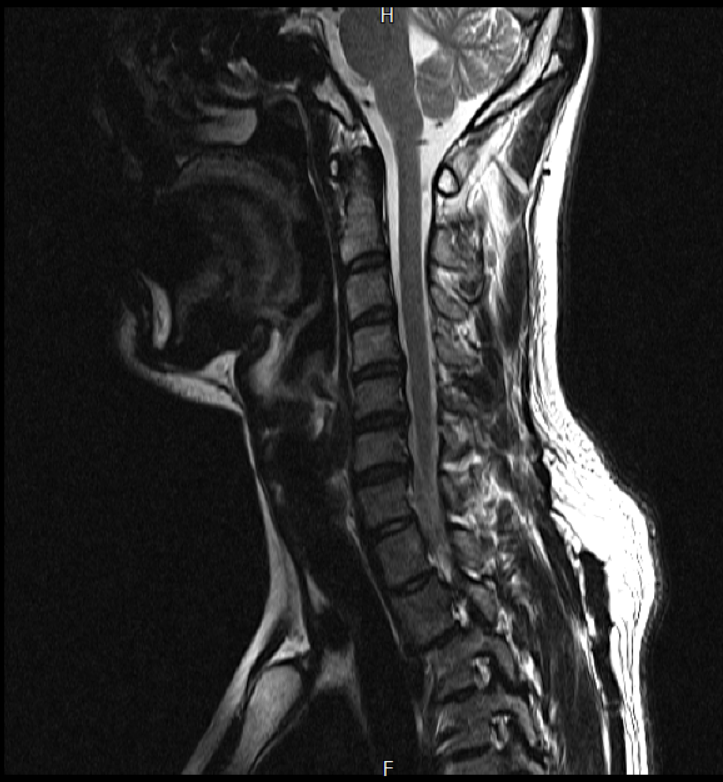

경추 요추 디스크 MRI판독 부탁드립니다.

-11월, 증상발생 직후 잠실소재 척추전문병원 MRI 요추경추 촬영 후 신경외과 박사 진료, 허리는 매우 건강, 경추는 퇴행성 진행되고 있지만 디스크라고 보기 어려움. 신경막만 살짝 건드리는 정도고 이 정도로 힘빠짐이나 저림이 오지 않고 원인은 다른 곳에 있을 가능성.

-올해 1월, 분당서울대병원 신경과 진료, MRI영상보더니 디스크가 있고 저림과 힘빠짐이 이에 기인했을 가능성이 충분히 있다고함. (경추만 말한것인지 요추도 포함인지 모르겠으나 디스크 시술 방안을 제시함) , 팔다리가 우연이 동시에 저림이 올수 있는지에 대해서 물었더니 이틀 상간으로 발생했기 때문에 동시라고 보기 어렵다고함...

1. MRI 상 , 경추와 요추에 디스크가 있나요? 있다면 좌측 팔과 다리에 저림 및 힘빠짐을 줄 정도인가요?

2. 혹시 영상의 퀄리티가 떨어져서 의사끼리 의견이 다른것일까요? MRI는 1.5T로 촬영된 것인데, 3.0T로 재촬영할 필요가 있을까요?

• 3번 째 사진

• 1. MRI 사진을 보았을 때 디스크를 의심해볼 수 있는 소견이 살짝살짝 보이긴 합니다만, 상하지의 저림 및 힘빠짐을 유발할 정도인지는 솔직히 회의적입니다.

2. 영상의 퀄리티는 나쁘지 않아 보입니다. 굳이 재촬영을 하실 필요는 없어 보입니다.

3. 개인적으로는 디스크로 인한 증상이 아닐 것으로 보나, 만약 디스크가 맞다면 우연하게 목과 허리 디스크 발병이 이틀 간격을 두고 나타났을 가능성을 생각해야 하는데, 현실적으로 그 가능성이 높지 않습니다.